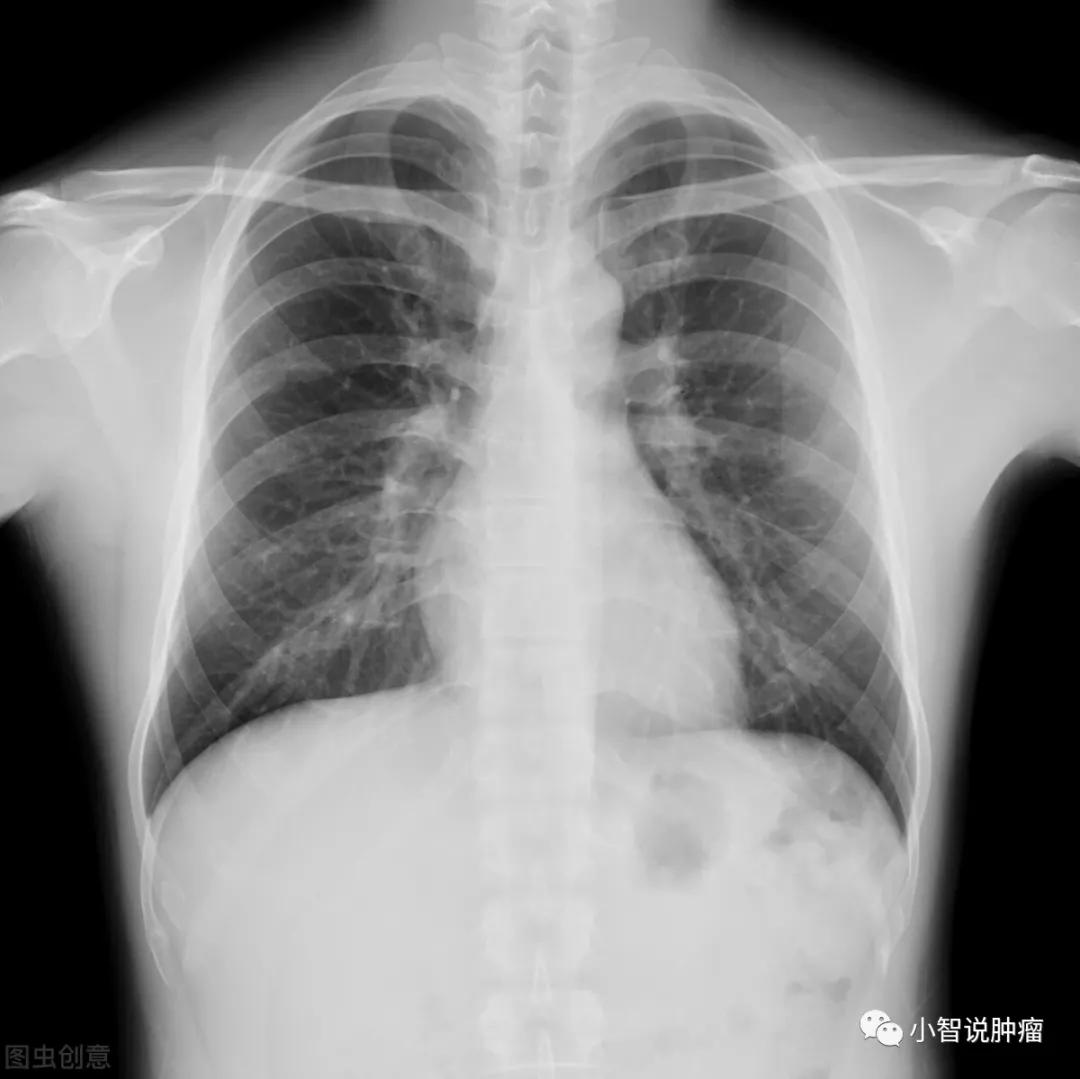

但是大问题还是来了:年年体检的老李头, 胸部普通X线检查 结果一直正常,怎么突然就查出了癌?难道体检没用吗?

体检健康,忽然查出癌症, 不是体检没有用,而是体检项目没做对!毫不夸张的说,目前,低剂量CT筛查(LDCT)是对早期肺癌筛查最有效的措施! 可是,老李头却一直只选择了胸部普通X线检查。

由于 普通胸部X线检查的价格较CT检查更便宜 ,很多患者觉得都是肺部检查,我直接做个胸片检查不也行么。

大家看这幅图片就能看出,普通胸部X线与低剂量螺旋CT最大的不同就是,它是 整体重叠的结构 ,而不是切片。由于前后组织结构的重叠干扰,这样就会导致隐藏在肺组织中间的微小病灶被遗漏,不利于肺癌的早期发现。

所以说,用CT筛查效果远比普通胸部X线检查好。